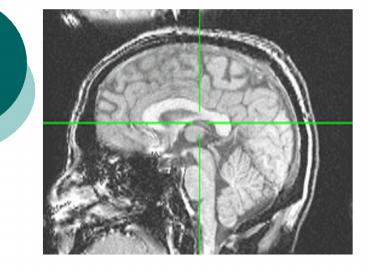

(No Transcript)